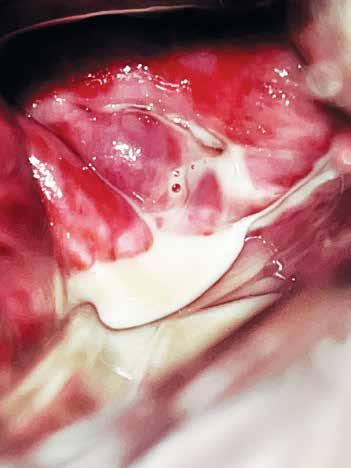

El cuello uterino está revestido por epitelio pavimentoso en su porción exocervical y epitelio cilíndrico en su porción endocervical. La unión de ambos epitelios es conocida como unión escamocolumnar (Figura 4.1).

La metaplasia escamosa del cuello uterino consiste en el reemplazo del epitelio cilíndrico mucíparo por epitelio escamoso estratificado y esto se produce a partir de las células de